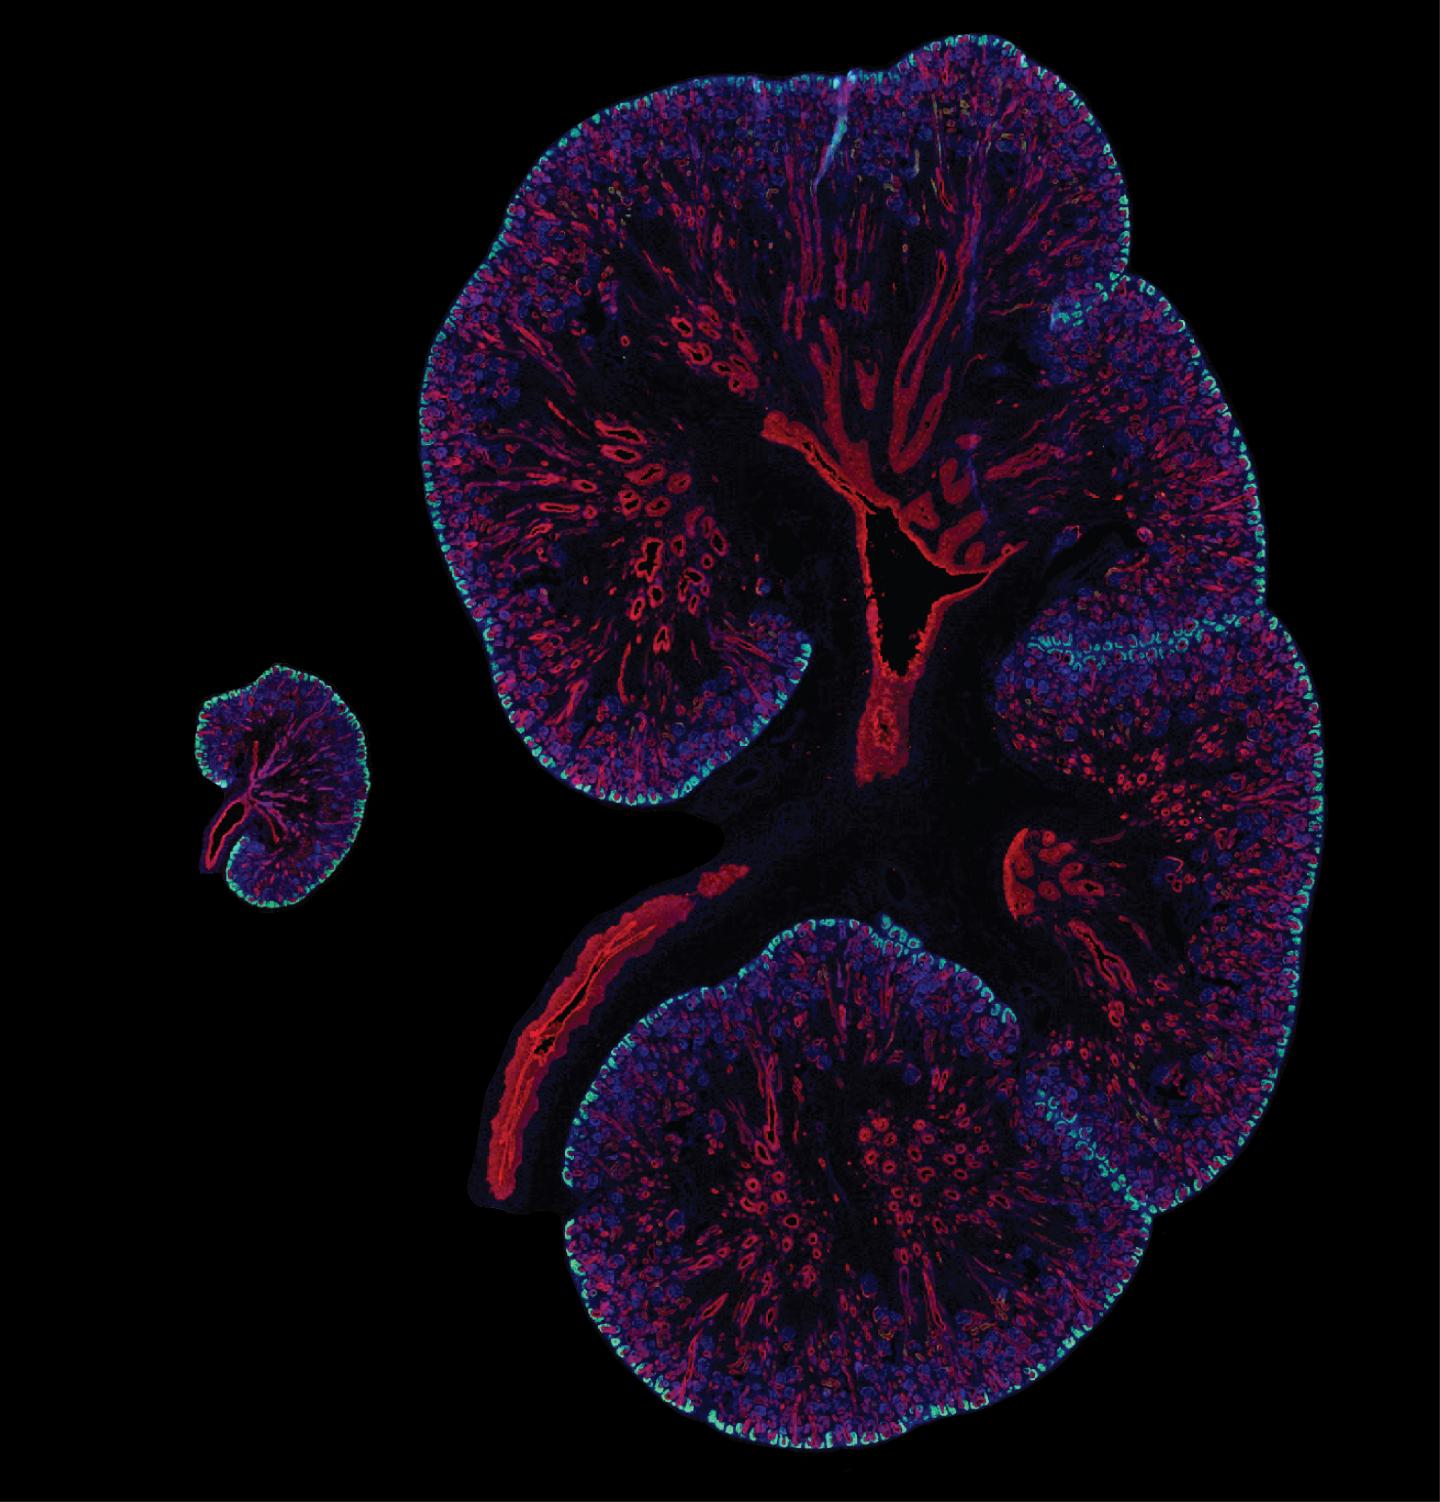

Embryonic day 15.5 mouse kidney next to a 15.5 week human fetal kidney with SIX2 (cyan) marking the nephron progenitor cells. The collecting duct system is red, and nuclei are in blue.